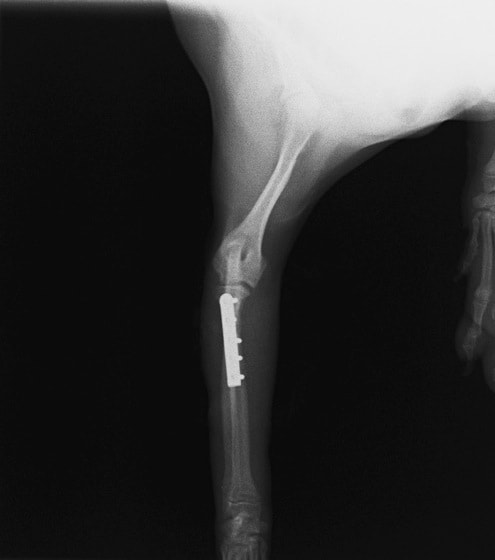

トイプードル 右遠位橈尺骨短斜骨折のALPSによる内固定

Locking Compression Plate

LCPは、スクリュー(ネジ)とプレート(金属の板)をロックする特殊な構造により骨折部位を固定する新しい世代のプレートシステムです。ひとつのホールでロッキングスクリューとスタンダードスクリューの使用を選択できるユニークな構造をしているため、骨折断端間の圧迫を目的とした従来型プレート固定法に加え、高い角度安定性を有するロッキングスクリューを用いた固定法の選択が可能です。従来のプレートシステムでは困難だった部分の骨折や癒合不全の症例に高い治療効果をもたらします。